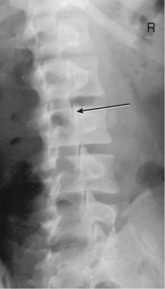

Scoliosis series (Ferguson method) (S)